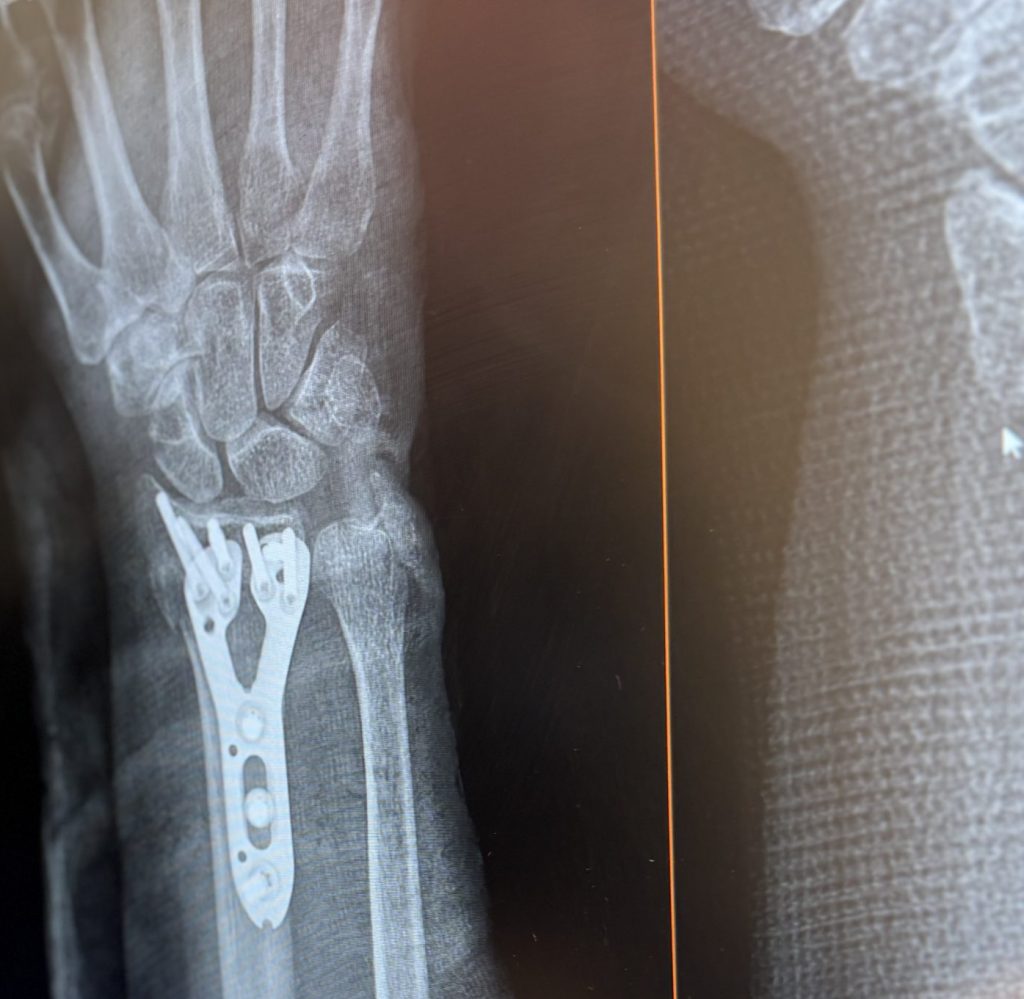

I broke my wrist and needed surgery ASAP - Dr. Abola and his assistant Jessica were so wonderful and squeezed me in for surgery in less than 1 week. Dr. Abola has a very kind bedside manner and made me feel very relaxed about everything - he explained the procedure and was honest about recovery and pain.